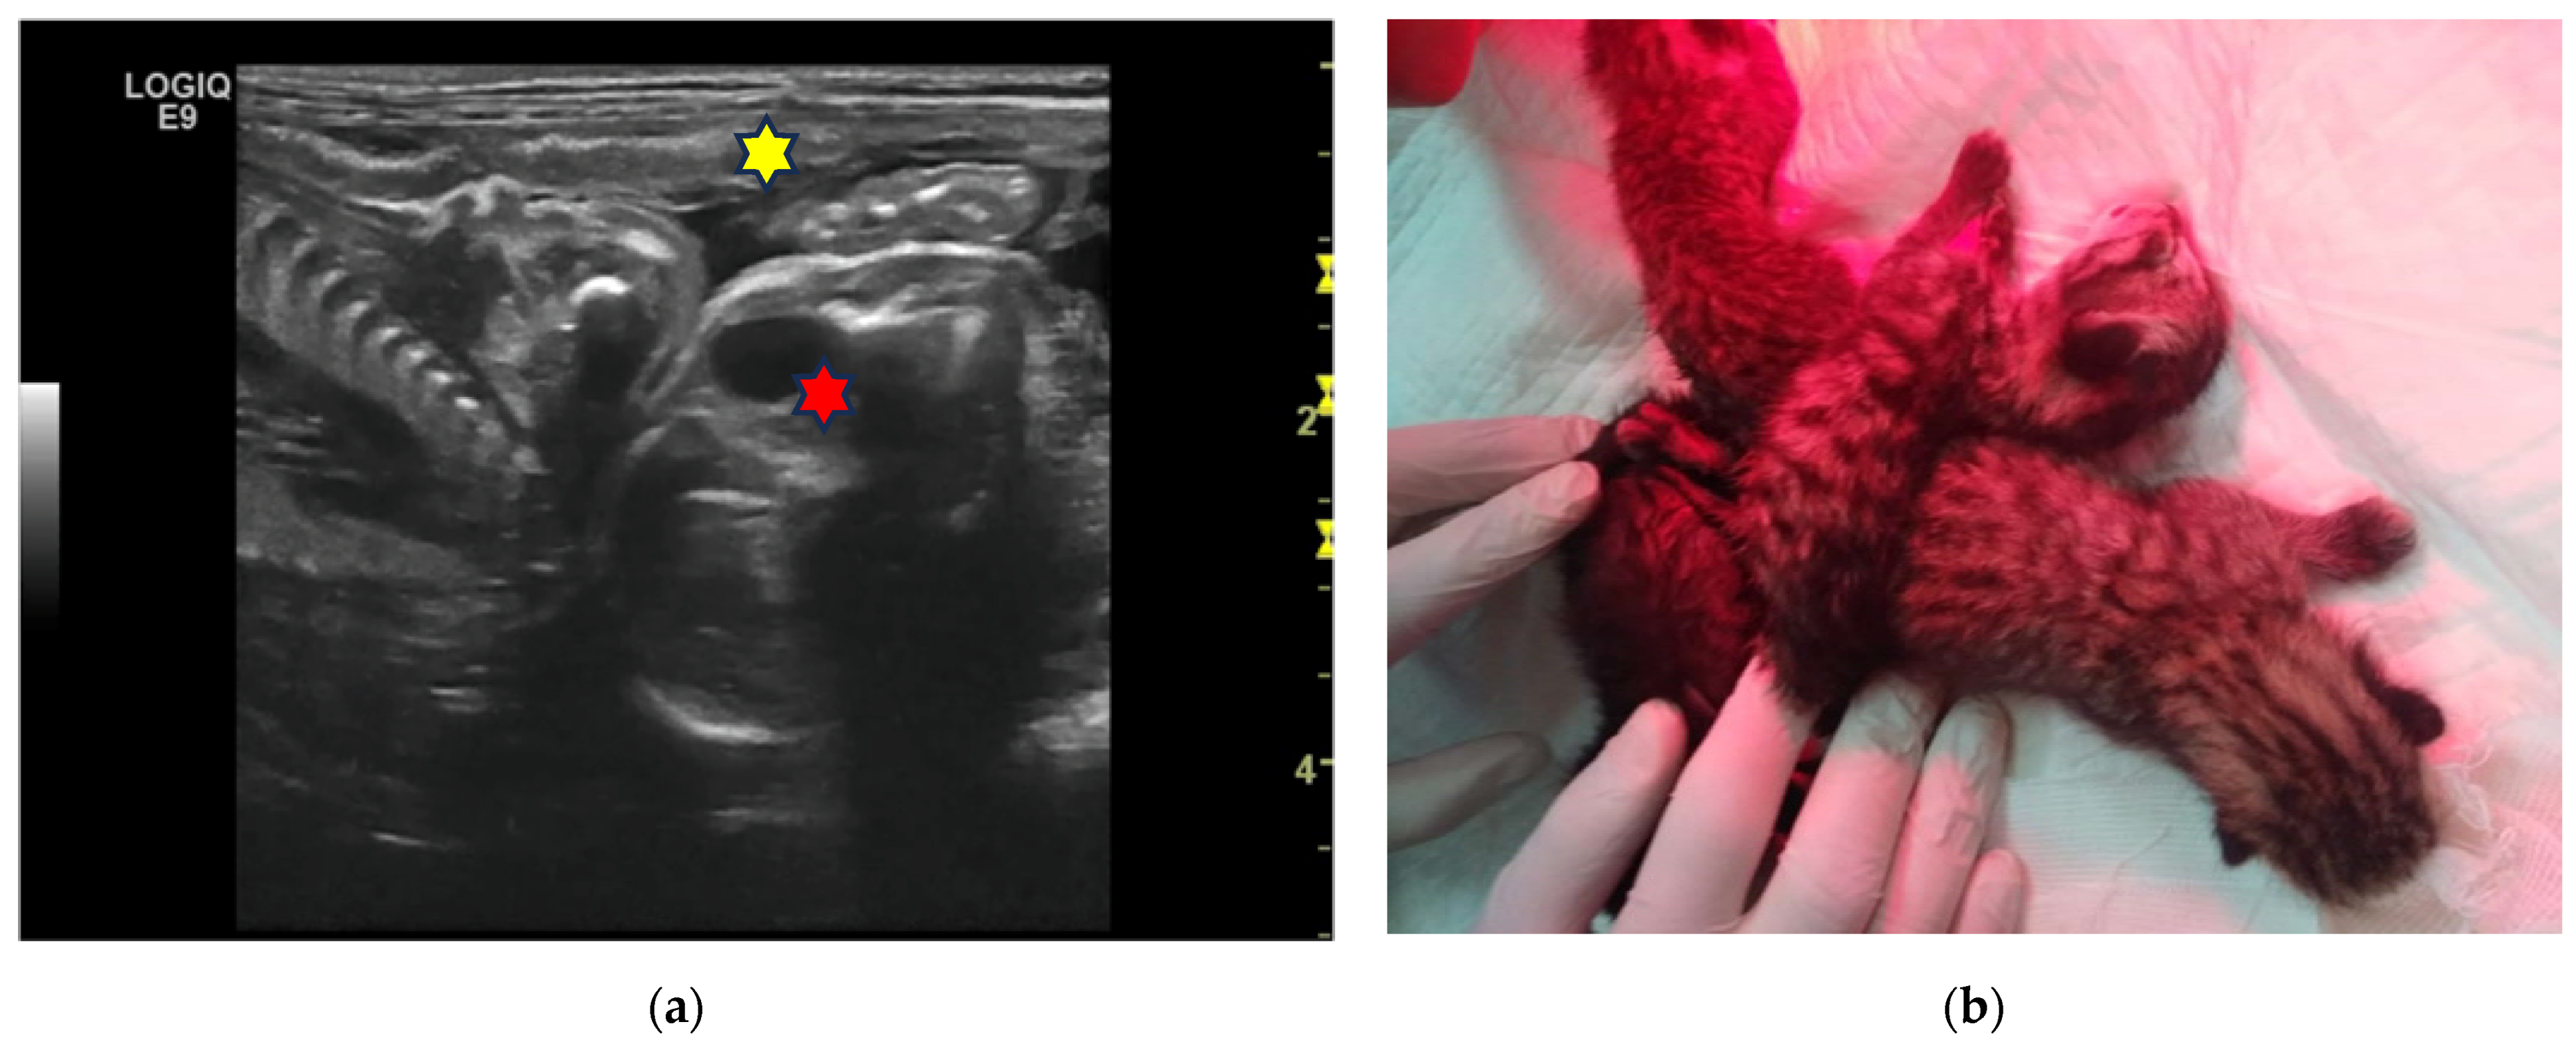

| 1F 2F | 6-year-old Birman female cat | 45 and 52 | 5 | Two pairs of monochorionic twins, morphologically comparable to the other foetus. | Natural delivery without assistance, three kitten stillborn. | One kitten dead for sepsis after 7 days. |

| 3F | 4-year-old European female cat | 50 | 4 | Monochorionic twins, morphologically comparable to the other foetuses. | Natural delivery without assistance, entangled neonates’ umbilical cords. | |